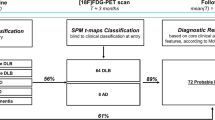

Compared with controls, SPM analysis in our nine sCJD patients showed hypometabolism in the medial parietal cortex bilaterally, and in the left-sided lateral and medial frontal (sparing Brodmann’s area 4 and 6, and the anterior cingulate cortex) and the lateral parietal cortex (Fig. 1). The brain area showing the most severe hypometabolism was Brodmann’s area 31 and to a lesser degree Brodmann’s area 23 (both areas correspond to the posterior cingulate cortex) and the precuneus. SPM analysis did not reveal basal ganglia or cerebellar hypometabolism. Basal ganglia hypometabolism was also absent on additional SPM analysis using a Gaussian kernel of 6 × 6 × 6 mm FWHM.

Compared with controls, SPM analysis (a and d are sagital views, b and e coronal views, and c and f axial views) in our nine sCJD patients showing the most severe hypometabolism in Brodmann’s area 31 (a–f large arrows) and to a lesser degree Brodmann’s area 23 and the precuneus, associated with hypometabolism in the left-sided lateral (a, b, c, and f, small arrowheads) and medial (b, c, d, and f, large arrowheads) frontal and lateral parietal (a, c, e, and f, small arrows) cortex

When present, cortical hypometabolism was lateralized in each lobe on individual patient analysis, resulting potentially in an underestimation of lateralized hypometabolism when confounding patients with different side predominance of hypometabolism. Therefore, we also performed separate SPM analysis in the group with left-sided predominant hypometabolism (n = 6) and in the group of patients with right-sided predominant hypometabolism (n = 3). In each of these groups, SPM analysis continued to show the posterior cingulate cortex (bilateral but predominant on the left side in the left-sided predominant group, and almost strictly unilateral on the right side in the right-sided predominant group) as the most hypometabolic area (Fig. 2). In the group with left-sided predominant hypometabolism, associated lateral and medial frontal and lateral parietal cortex hypometabolism involved larger areas extending into the lateral posterior temporal cortex (Fig. 2), whereas in the group with right-sided predominant hypometabolism only small zones of associated lateral frontal hypometabolism were seen (Fig. 2).

SPM analysis in the group with left-sided predominant hypometabolism (a–c) and in the group of patients with right-sided predominant hypometabolism (d–f) continued to show medial parietal cortex hypometabolism in both groups. In the group with left-sided predominant hypometabolism, associated lateral and medial frontal and lateral parietal cortex hypometabolism involves larger areas extending into the lateral posterior temporal cortex (a–c), whereas in the group with right-sided predominant hypometabolism only small zones of associated lateral frontal hypometabolism is seen (d–f)